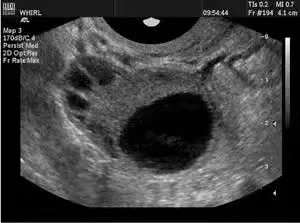

卵巢最主要的功能是产生卵子,卵子在卵泡里和卵泡同步发育,我们通过观察卵泡来推测卵子的发育情况。卵巢的皮质内有多个直径﹤10mm的小卵泡回声,称之为窦卵泡,当窦卵泡直径超过10mm便成为生长卵泡,当生长卵泡继续增大就成为了医生常说的优势卵泡。

通常每月只有一个优势卵泡,当优势卵泡﹥18mm则成为成熟卵泡。而卵泡监测则是在超声介导下对卵泡的直接观察,卵泡监测是一个动态的过程,每周期需要至少3-4次的超声监测。监测卵泡检查虽然看起来比较麻烦,但是评估卵泡最直观的方法,具有重要的临床意义。

月经8-10天:常规开始监测卵泡,隔2-3天监测;卵泡﹥15mm时:每天或隔天监测,卵泡18-20mm时,为成熟卵泡,此时可诱导排卵;

·成熟卵泡消失或者明显缩小

·卵泡壁不规则、增厚、边缘皱缩,内充满细小弱光点。

·盆腔少量积液,一般﹤1cm,2-3天消失。

总之,卵泡太小、卵泡过大、不排卵、卵泡形态不规则均是卵泡发育异常的超声表现。超声监测排卵简单、可靠、无需做特殊准备。